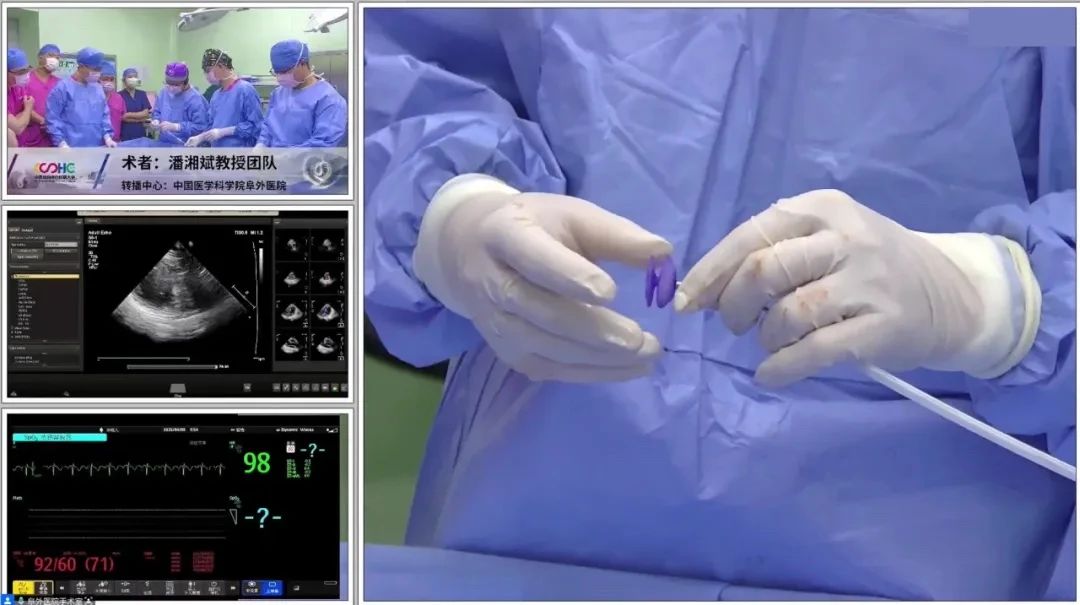

体外装载可降解PFO封堵器

为减少大鞘在心房内停留时间,可提前装载封堵器。两例手术均在单纯超声指导下开展,第二例患者术中通过导管配合超声导丝法顺利过隔,第一例患者经导管导丝探查法尝试过隔未果后,改用鞘管配合导丝法。术中所采用的PannaWire超声专用导丝为两例手术的新利器,其头端呈梭型,超声很容易探测,具有较佳的指向性,既降低了过隔难度,又提升了操作安全性。对于第一例患者,经超声确认导丝头端位于卵圆窝附近后,保持鞘管头端垂直指向房间隔方向缓慢推送,待导丝头端影像消失即提示鞘管已成功贴靠卵圆窝,后在其支撑下,导丝顺利过隔,建立股静脉至左心房的导丝轨道。

完成导丝轨道建立后,置入输送鞘。封堵器经鞘顺利送入左房后,在超声引导下先释放左盘面,通过牵拉成型线使其由“灯笼状”变为“盘状”,再回撤钢缆,使左盘紧贴房间隔。待右盘面释放后牵拉成型线,若超声下观察到右盘随房间隔摆动,且双盘贴合于间隔、形态合适,即开始锁定。成型锁定后,超声下双盘面紧紧扣合在房间隔两侧,形态良好,且轻轻牵拉钢缆,双盘相对位置保持不变,依然紧贴合房间隔,判定锁定成功。